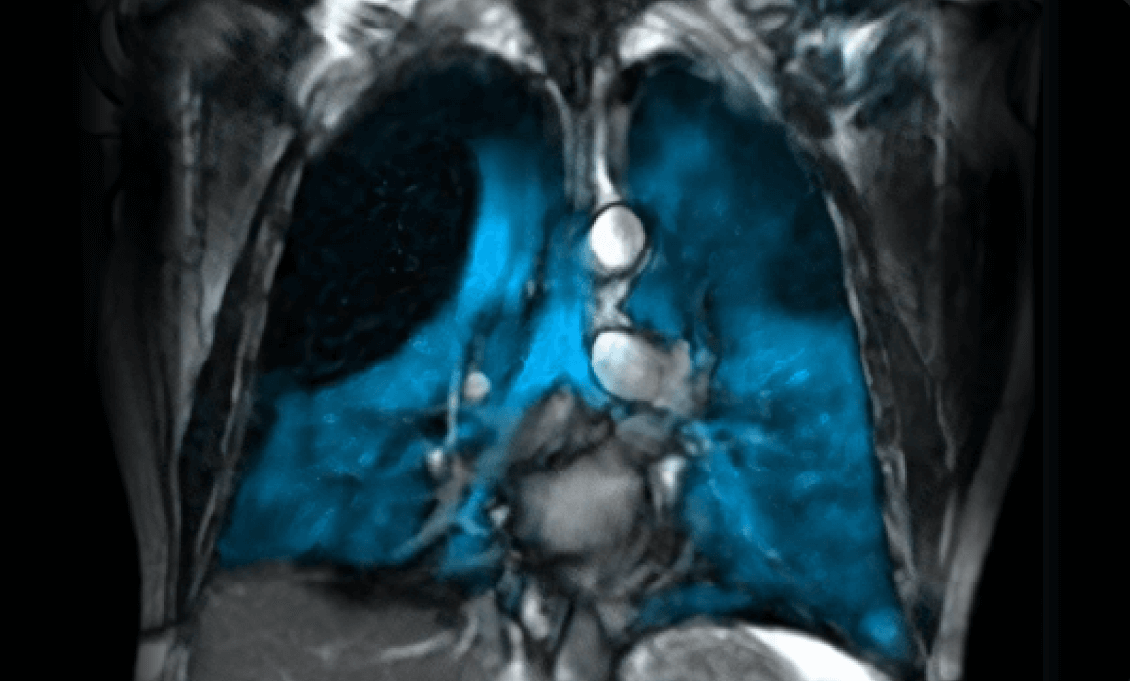

xenoview mri

The UAB Center for Lung Analytics and Imaging Research (CLAIR), in collaboration with the Research MRI Core (RMRIC), has successfully performed the first Xenon-129 MRI lung imaging at UAB.

This achievement, led by Surya Bhatt, M.D., director of CLAIR, and Mark Bolding, Ph.D., MRI director of CLAIR and RMRIC physicist, positions UAB as the only facility in the region with this revolutionary FDA-approved technology.

"This isn't just a new scan; it is a game-changer,” said Bolding. “With a single 10-second breath-hold and zero radiation, we are now able to map lung function at the molecular level."

Xenon MRI uses hyperpolarized xenon gas to create detailed functional images of lung ventilation without ionizing radiation, making it safe for both adults and children. The technology, implemented using  state-of-the-art hyperpolarizer system, enables visualization of ventilation defects and gas exchange abnormalities invisible to conventional imaging. This opens unprecedented opportunities for early disease detection, treatment monitoring, and research into conditions including COPD, asthma, cystic fibrosis, and post-COVID lung complications.